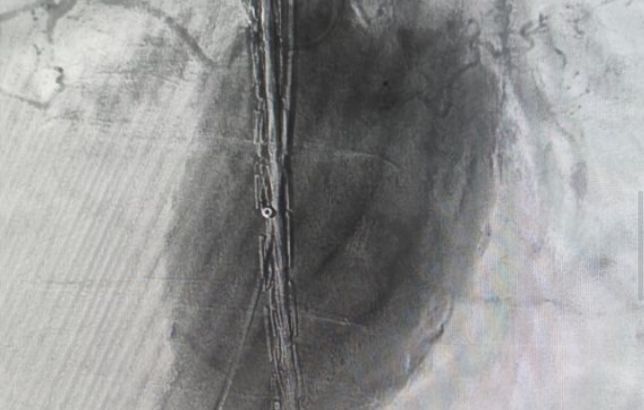

По множеству противопоказаний открытое вмешательство подвергло бы жизнь пациента высокому риску. Специалисты приняли решение о применении эндоваскулярного метода для установки стент-графта. «Стент-графт – комбинация стента (металлической или...